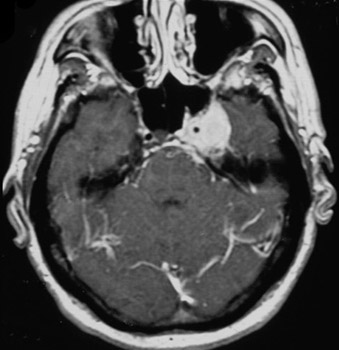

Meningioma

Imagem axial captante de contraste demonstra meningioma no seio cavernoso no lado esquerdo

Da biblioteca pessoal do Dr. William T. Couldwell; usada com permissão